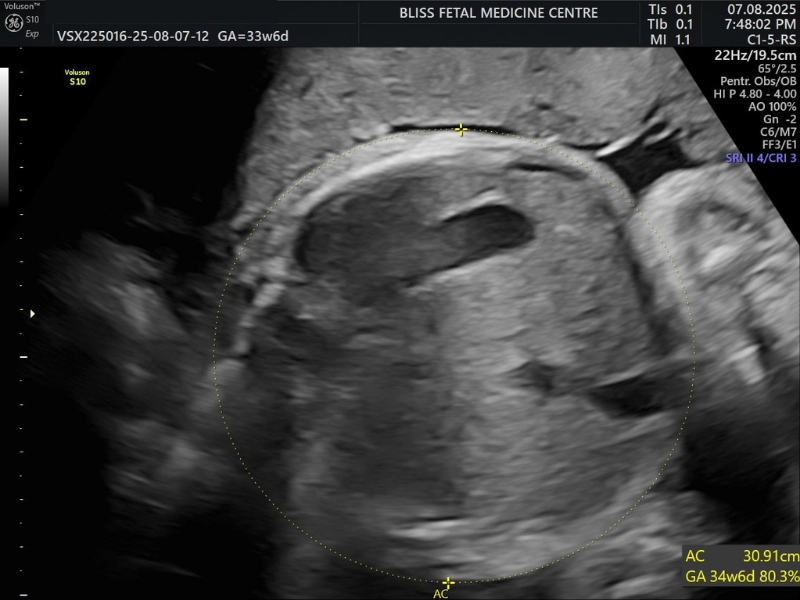

4. Detailed Anomaly Scan

The Detailed Anomaly Scan is similar to a standard ultrasound scan but provides detailed information. Here, fetal anatomy is assessed to ensure that the baby develops normally, especially by measuring the parts of the body to see how well it is growing.

When Is It Performed?

- It is a second-trimester scan performed between 18 and 23 weeks.

- It helps determine the presence of Spina Bifida (Open Spinal Cord).

- It is also done when special attention is needed for the baby’s brain, face and other vital organs.